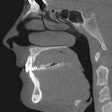

Study: Dentists need to consider diagnostic task in CBCT use